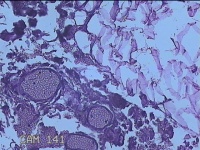

外阴部包块

性别

女

年龄

37岁

临床诊断

皮脂腺囊肿

一般病史

外阴部起包块一月余。

标本名称

大体所见

灰白暗红色包块2.3x1.8x0.8cm一个,表面糜烂,切开包块呈实性,切面灰白淡黄色,质软。

图3